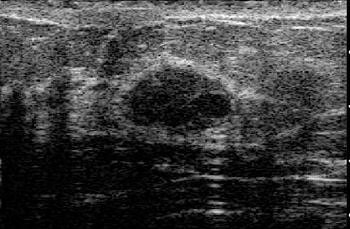

![]() |

| Fibroadenoma with elasticity score of 2 in 39-year-old woman. US images were obtained in transverse plane. Left: On conventional B-mode image, lesion was classified as BI-RADS category 3. |

| On elasticity image, hypoechoic lesion shows mosaic pattern of green and blue. Figure 3. Ako Itoh A, Ueno E, Tohno E, et al, "Breast Disease: Clinical Application of US Elastography for Diagnosis" (Radiology 2006;239:341-350). |